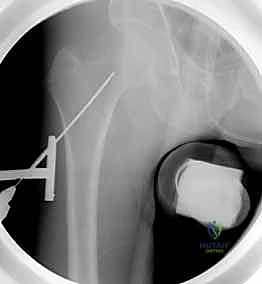

خطوات العملية الجراحية مع الأستاذ الدكتور محمد هطيف

1. التجهيز والتخدير (Preparation & Anesthesia)

يتم تخدير المريض (غالبًا تخدير نصفي/شوكي، أو تخدير عام حسب الحالة). يُوضع المريض على طاولة عمليات خاصة تُسمى "طاولة الشد العظمي" (Fracture Table). تتيح هذه الطاولة للدكتور هطيف تطبيق شد دقيق على الساق لرد الكسر إلى مكانه الطبيعي دون الحاجة لفتح الجلد.